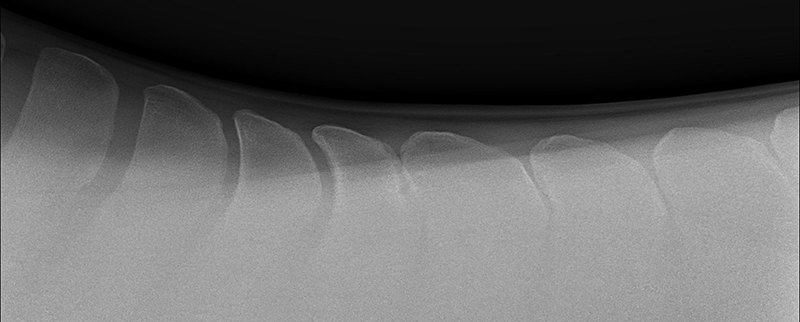

Kissing Spines, more scientifically known as impingement of the dorsal spinous processes, is a condition that has grown in relevance and impact throughout the last two decades with improved diagnostics and education. It’s hard not to feel a horse’s pain after taking just one look at an x-ray that indicates Kissing Spines. The condition can diminish athletic performance and render a horse unusable in severe cases, while other cases with the ugliest x-rays can experience no pain or performance implications. While still shrouded in some level of mystery, Kissing Spines is known to be conformational and most likely genetic. When spinous processes are conformationally close together they will inevitably contact, with that continual contact causing the modeling changes that are classically seen on radiographs.

Though Kissing Spines can be seen clearly in diagnostic imaging, truly understanding the nuances of the condition and how it can vary patient-to-patient is where things become less well-defined. Dr. Cliff Honnas, equine veterinarian, surgeon and founder of the widely respected Texas Equine Hospital in Bryan, Texas, is a sought-after authority figure in all things related to this condition, especially concerning its surgical treatment. “Kissing Spines is a condition where the dorsal spinous processes are too close together,” he explains simply. “These are the bones that make up the backbone of the horse directly underneath the saddle.” Normal horses should typically have a five millimeter or larger space between those bones, depending on the breed and size of the animal in question. In Kissing Spines cases, however, that space can be minimally to drastically narrowed until those bones are close together, touching or overriding.

While there are numerous conditions impacting the equine back, the diagnosis of Kissing Spines has increased fairly dramatically in recent years thanks to improved diagnostic techniques coupled with a greater focus on veterinary education. “Depending on who you choose to believe in the literature, Kissing Spines along with dorsal articular facet arthritis will account for 50 to 70 percent of orthopedic back problems,” says Dr. Kent Allen, sports medicine practitioner, founder of Virginia Equine Imaging, FEI Olympic-level veterinarian, current Vice President and Executive Director of ISELP and Chairman of the USEF (United States Equestrian Federation) Veterinary Committee. “The horse, which of course has a horizontal back as opposed to a human’s vertical back, doesn’t have disk problems like we do but rather has bony orthopedic problems that impact the way they bend, extend and jump, such as Kissing Spines and arthritis of the dorsal articular facets,” explains Dr. Allen. “In terms of Kissing Spines specifically, its location is most commonly from the base of the withers back to the thoracolumbar junction, from T16 back to L2-3. In contrast, arthritis of the articular area will often occur further back, about three inches forward to three inches behind the rear of an English Saddle.” While the general location and disease process have become more solidified, the clinical presentations exhibited by affected horses are wide-ranging and can create significant diagnostic and treatment challenges for veterinarians.

A condition where the dorsal spinous processes are too close together. Typically horses have about a five millimeter space between those bones; however, in Kissing Spines cases, that space is narrowed until those bones are close together, touching or overriding.

While the clinical signs of Kissing Spines can be ambiguous, Dr. Allen is quick to point out that not all horses with radiographic evidence of the condition display outward signs. “It's often a question of when this condition presents or if it presents. If we’re talking about a western pleasure horse or a horse that doesn’t ever jump over 2 feet 6 inches in its life, the animal may have Kissing Spines and never present. A look at the data on hundreds of horses with back pain revealed that the average age of presentation of back pain was about 6.5-years-old.”

While horses may be genetically predisposed to Kissing Spines and present clinical signs on an x-ray as early as 2-years-old, there are a great number of factors that go into determining if that horse will ever become clinical, including its level of training and specific discipline. Horses performing a sport that requires a high amount of flexing and bending of the back will oftentimes have increased odds of developing clinical symptoms of Kissing Spines in comparison to low-impact or more leisure-based sports — think of a cutting horse versus a horse primarily used on the trail. “A common situation is that we’ll see a horse come in for a pre-purchase exam, and since we’ll routinely do a back x-ray now, we’ll often see some degree of Kissing Spines,” says Dr. Honnas of a frequent and tough place that equine veterinarians find themselves in with potential buyers. “This could mean that space between those bones is reduced but very often not actually touching or overriding. We can also see horses that have tremendous Kissing Spines on an x-ray, but clinically are virtually normal and have no history of back pain. It makes it very difficult to decide on a pre-purchase exam what to recommend to the potential buyers in terms of their risk. This can be a top-end horse, doing its job well and with no disability. We’ll pick up Kissing Spines to some degree on the x-ray, and it’s impossible to state with certainty that horse’s risk of developing symptoms in the future.”

Following a thorough whole-body physical examination and a more specialized motion evaluation, the next step in a suspected case of Kissing Spines is to confirm the diagnosis with imaging. Drs. Honnas, Story, Williams and Allen are all significant proponents of the importance of those initial examinations prior to performing imaging. “I tell my clients, ‘I can x-ray your horse's back and look for things like Kissing Spines, but that could be just a tip of the iceberg,’ ” says Dr. Williams. “That comprehensive evaluation is absolutely necessary to form a complete picture.”

There are two primary diagnostic imaging methods that deliver the clearest picture — literally and figuratively — when dealing with a potential Kissing Spines case. “I teach combined imaging using x-ray and ultrasound to look at as much of the tissue as possible,” says Dr. Williams of his approach. While Kissing Spines can oftentimes appear clearly using x-ray alone, the use of this combined imaging approach delivers the most definitive diagnosis possible. “Ultrasound is the most sensitive tool to observe surface detail. It reflects off of bone. You can't see through it, but if the bone surface is uneven, it will tell you that. On an x-ray or a radiograph you can’t pick that up unless you get the perfect view,” says Dr. Williams of one reason he brings ultrasound into the equation. Another attribute of ultrasound is its ability to look at the supraspinous ligament, multifidus muscles and the facet joints, which are placed further down at the base of the spinous processes. “I talk about ultrasound surveys,” says Dr. Williams. “I don't just look with the ultrasound, then find something and walk away. I survey the back from the withers all the way back through the lumbar region. This gives me all of the information, and I can then better determine whether the horse has Kissing Spines alone, if the case is surgical and if there’s something else at play in addition to the Kissing Spines.”